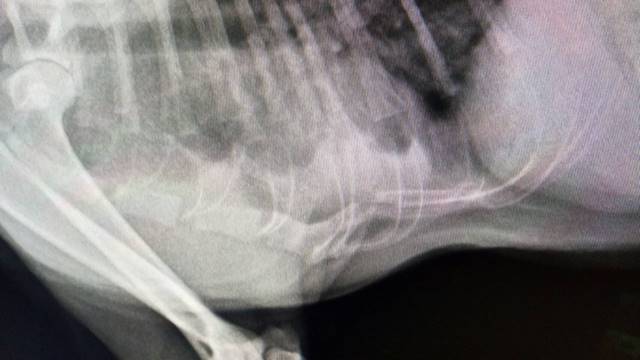

經過了3天,昨天他晚上終於出現但感覺就是沒有精神及元氣,經我初步檢視他的外觀,發現下巴好像腫漲,有出血過,於是趕快送到醫院做更進一步檢查。結果血檢出肝指數異常的飆高,再進一步照X光,才發現原來肋骨斷裂,且心臟部分有出血,有生命危險,推斷可能是出了車禍,現在以氧氣點滴抗生素治療,希望能止住出血讓他能儘快恢復。動物近況說明: 斑斑住院三天內算是危險期,不過他食慾和精神都很好,體力也慢慢地恢復,住院一週後,也無異常狀況發生,所以照預定期間住院二週後出院,出院前為確保他復原正常又再拍了一次X光,確認已沒內出血的問題,也幫他打了預防針後,接回素食攤老闆娘家中靜養,目前一切都很正常。